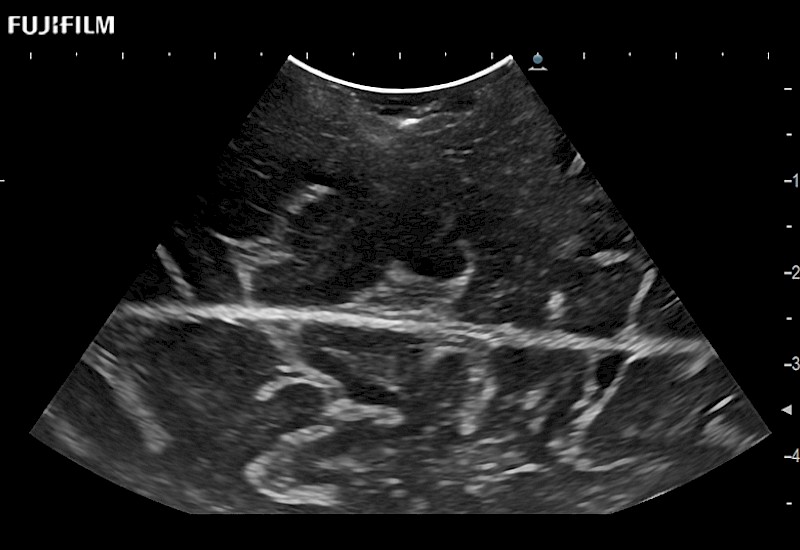

Hockey-stick linear array transducer is the transducer of choice for cervical spine scanning.

Main Specifications: